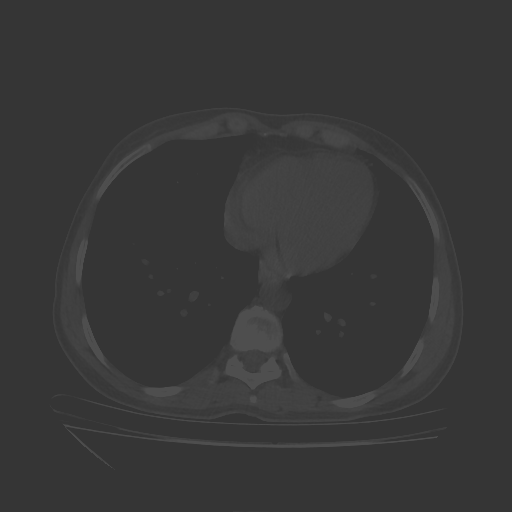

Reconstructed NATIVE CT scan (cycle consistency)

No window - Raw intensity values

Lung window (WL -600, WW 1500 β†’ Low βˆ’1350, High +150)

Mediastinum window (WL 40, WW 400 β†’ Low βˆ’160, High +240)